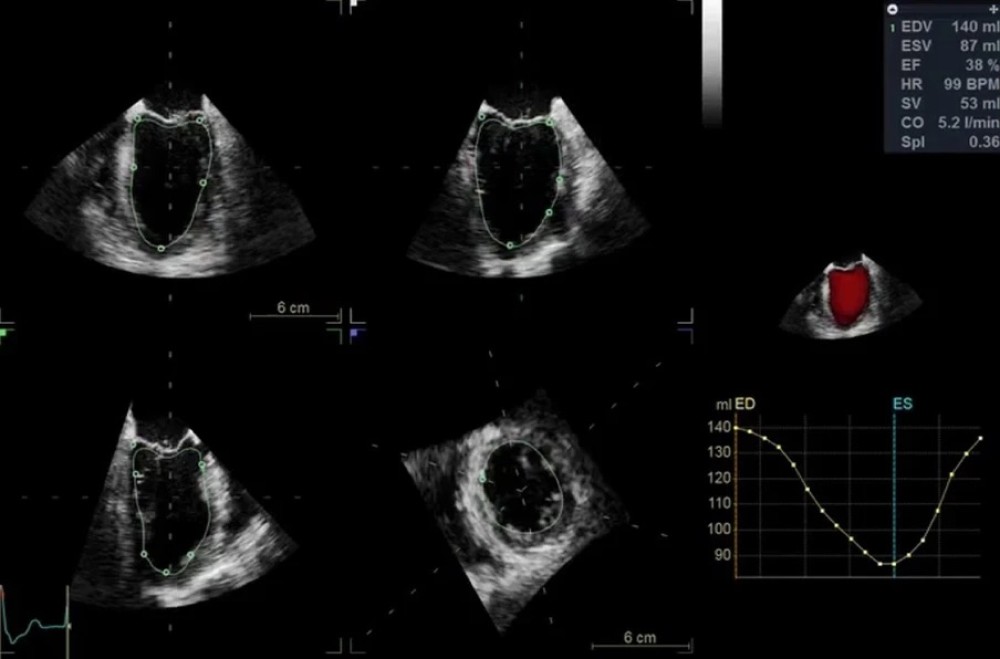

4D Auto LVQ — sol ventrikulun 4D avtomatik kvantitativ analizi

GE Vivid S70N Dimension — mütəxəssis kardiologiyası üçün nəzərdə tutulmuş inkişaf etmiş ultrasəs sistemi. Bu model təkmilləşdirilmiş 4D ekokardioqrafiya funksiyalarına malikdir və matriks  (TEE) problarını dəstəkləyir. Sistem həmçinin kvantitativ həcmli məlumatların təhlili və qiymətləndirilməsi üçün geniş alətlər toplusunu təmin edir.

cSound platforması əsasında işləyən Vivid S70N Dimension ürək və damar strukturlarının yüksək dəqiqlikli görüntülənməsini təmin edir, beləliklə kardiologiya üzrə mütəxəssis mərkəzlər, funksional diaqnostika şöbələri və yüksək diaqnostik dəqiqlik tələb edən tibb müəssisələri üçün ideal seçimdir.